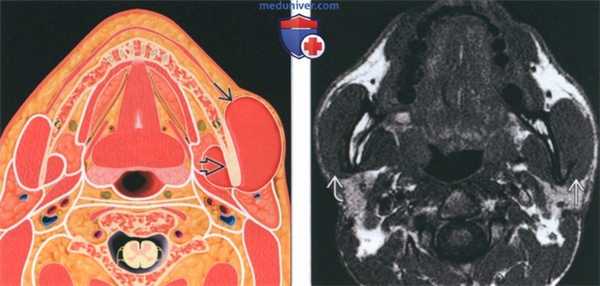

(Слева) На фотографии пациента с односторонней доброкачественной гипертрофией жевательной мышцы можно увидеть обширное равномерное выбухание щеки, обусловленное увеличенной жевательной мышцей в области прикрепления к углу нижней челюсти.

(Справа) На аксиальной МРТ (Т2) у пациента с типичной односторонней доброкачественной гипертрофией жевательной мышцы определяется увеличение жевательной и медиальной крыловидной мышц с сигналом, идентичным мышцам слева.

(Слева) На рисунке в аксиальной плоскости показано одностороннее увеличение левой жевательной мышцы. Обратите внимание на утолщение кортикальной пластинки нижней челюсти. Сравните с неизмененной жевательной мышцей и нижней челюстью с противоположной стороны.

(Справа) МРТ (Т1), аксиальная проекция: в этой же области определяется диффузное увеличение левой жевательной мышцы по сравнению с противоположной стороной.

(Слева) При МРТ Т1ВИ в коронарной проекции отмечается увеличение правой височной мышцы у пациентки, обеспокоенной косметическим дефектом, который становится заметным при забранных в хвост волосах. И хотя чаще встречается гипертрофия жевательной мышцы, увеличиваться в размерах может и любая другая мышца.

(Справа) При МРТ Т1FS с КУ в аксиальной проекции у этой же пациентки сигнал от увеличенной мышцы имеет нормальную интенсивность, контраст не накапливается.